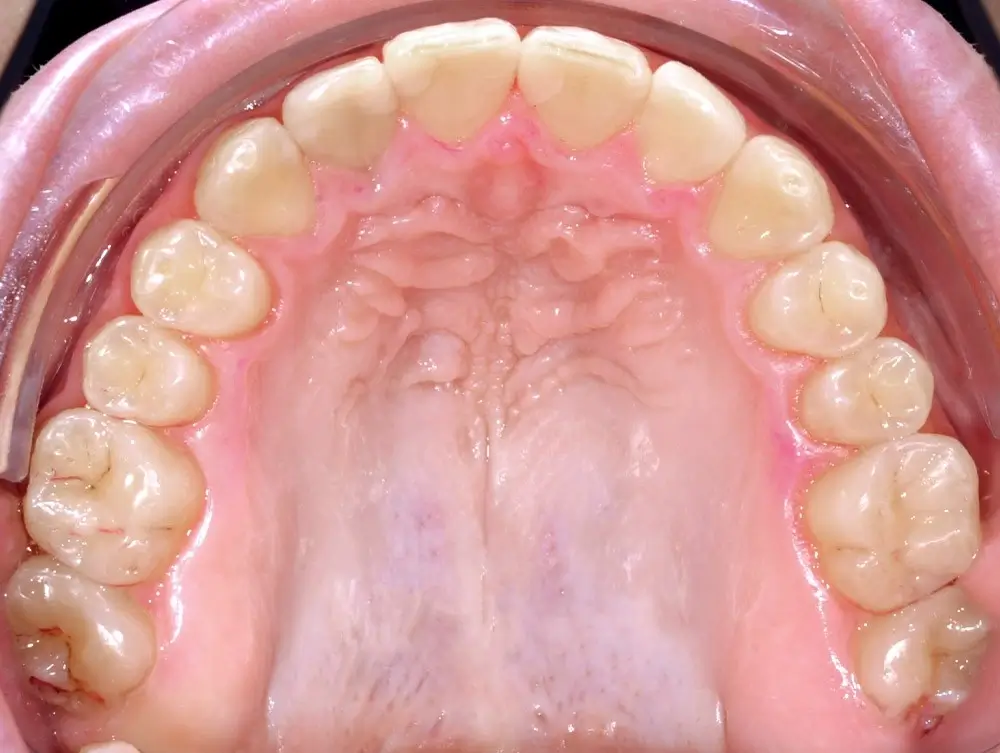

Открытый прикус - Кейс 2

Эффективность устранения дефекта прикуса посредством элайнеров FlexiLigner.

22

Количество кап ВЧ

Результаты лечения